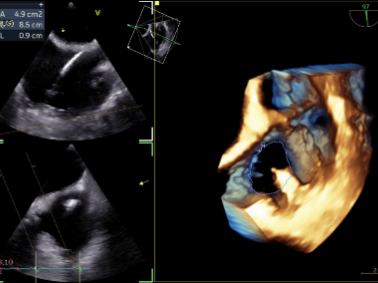

Preoperative Regurgitation: 4+

Annulus Area: 11.3 cm²

Postoperative Regurgitation: 1+

Annulus Area: 4.9 cm²